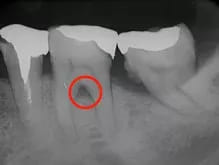

CT/レントゲン検査

歯周病は顎の骨を溶かしてしまう病気です。その進行状況を正確に把握するために、CT検査を行います。CTは3Dで立体的な画像を撮影できる装置で、歯周病の進行度を詳しく調べることができます。

根分岐部病変とは、歯の根の分かれ目にまで歯周病が進行した状態を指します。歯と歯茎の間に隙間があり、この部分に歯石がたまると通常の器具では届きません。